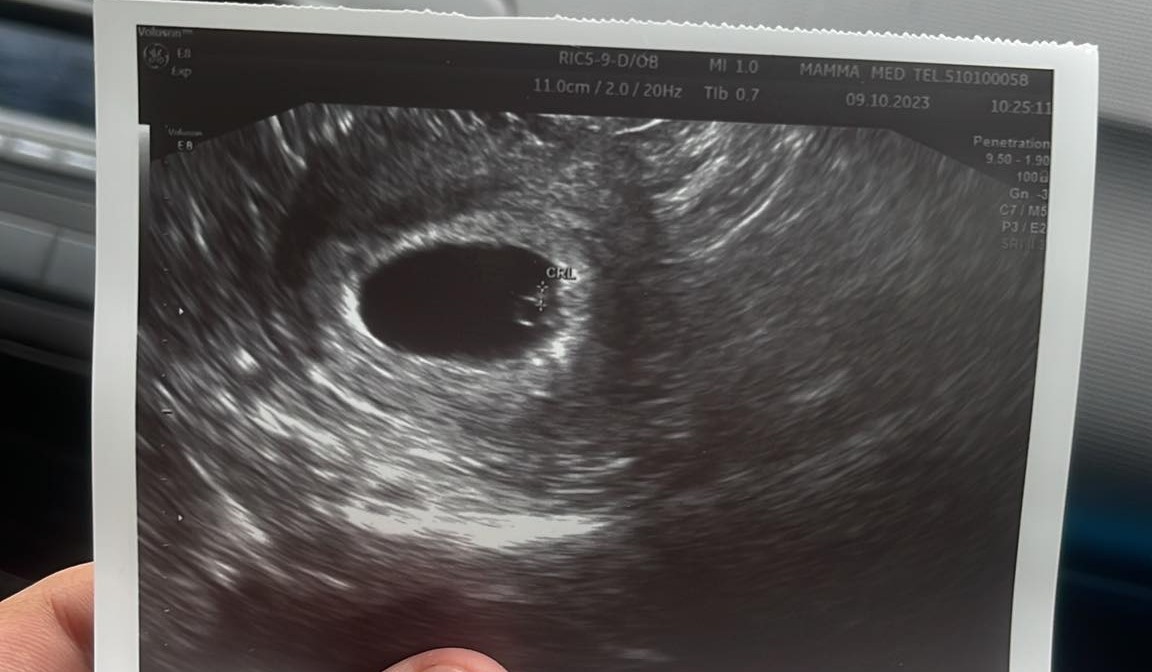

Maluch ma już 3mm, serduszko pięknie widoczne i bije

Mocno przytulił się do ściany macicy więc ledwo go widać ale serce nawet na oddaleniukolejna wizyta za 3 tygodnie